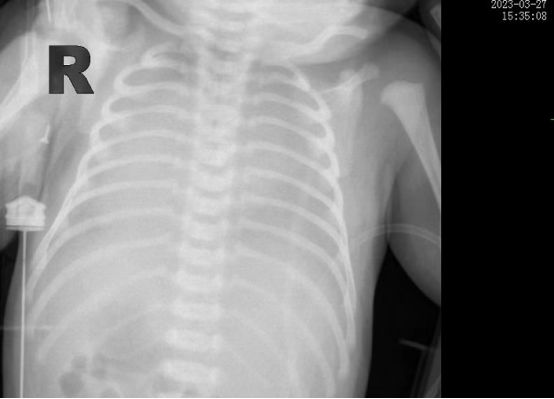

時間追溯到3月27日,該患兒出生時哭聲欠連貫,全身可見黃色胎糞附著,羊水三度污染,呼吸稍促,血氧飽和度低,立即被轉(zhuǎn)入新生兒科。醫(yī)生立即予以清理呼吸道,常壓給氧,建立靜脈通道后抱入暖箱復溫,同時以無創(chuàng)輔助通氣。然而患兒呼吸窘迫癥狀正在進行性加重,胸片提示“白肺”,結(jié)合血氣分析等檢查后,患兒被診斷為“急性呼吸窘迫綜合癥”、“呼吸衰竭”。時間就是生命,主管醫(yī)生張海嬌在與家屬充分溝通同時,副主任醫(yī)師鐘玉芬立即帶領(lǐng)新生兒醫(yī)護團隊快速采取急救措施,給予患兒氣管插管術(shù)進行有創(chuàng)呼吸機高頻震蕩通氣,并從氣管內(nèi)滴入PS(肺表面活性物質(zhì)),以降低肺泡表面張力,增加肺順應性,患兒血氧這才穩(wěn)定下來。

在科室團隊的共同努力下,患兒歷經(jīng)5天有創(chuàng)通氣5天無創(chuàng)通氣,再調(diào)整為5天吸氧后已經(jīng)實現(xiàn)呼吸自由,復查肺部CT,終于看到白肺已云開霧散。4月15日,歷時17天的醫(yī)療救治,患兒順利出院,回到了媽媽的懷抱。